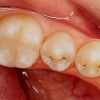

Emailikaaries on pindmine kahjustus, mille puhul karioosne defekt asub emailis. Märgatav on piimjasvalge värvusega defekt, harvem pigmenteerunud hambapind. Viimast võib leida purihammaste hambavagudes ehk fissuurides.

Dentiinikaaries on dentiinikihti osaliselt haarav defekt e. hambaauk milline ulatub emaili all hambaluusse. kuid pulbi kaitseks jääb veel küllalt kahjustamata kudet. Võrreldes emailiga on dentiin vähem kaltsifitseerunud ja sisaldab mikroskoopilisi õõnsusi (tuubuleid), mistõttu allub kergemini hapete ja mikroobide mõjule ning kaaries kulgeb seal kiiremini.

Sügav dentiinikaaries on pulbi lähedusse ulatuv sügav karioosne defekt, mille juures dentiini kiht pulbi kaitseks on jäänud väga õhukeseks. Sellise kahjustuse puhul võib esineda kaebus valule, mis tekib teravamaitselise toidu ja külma-kuuma ärritusele.